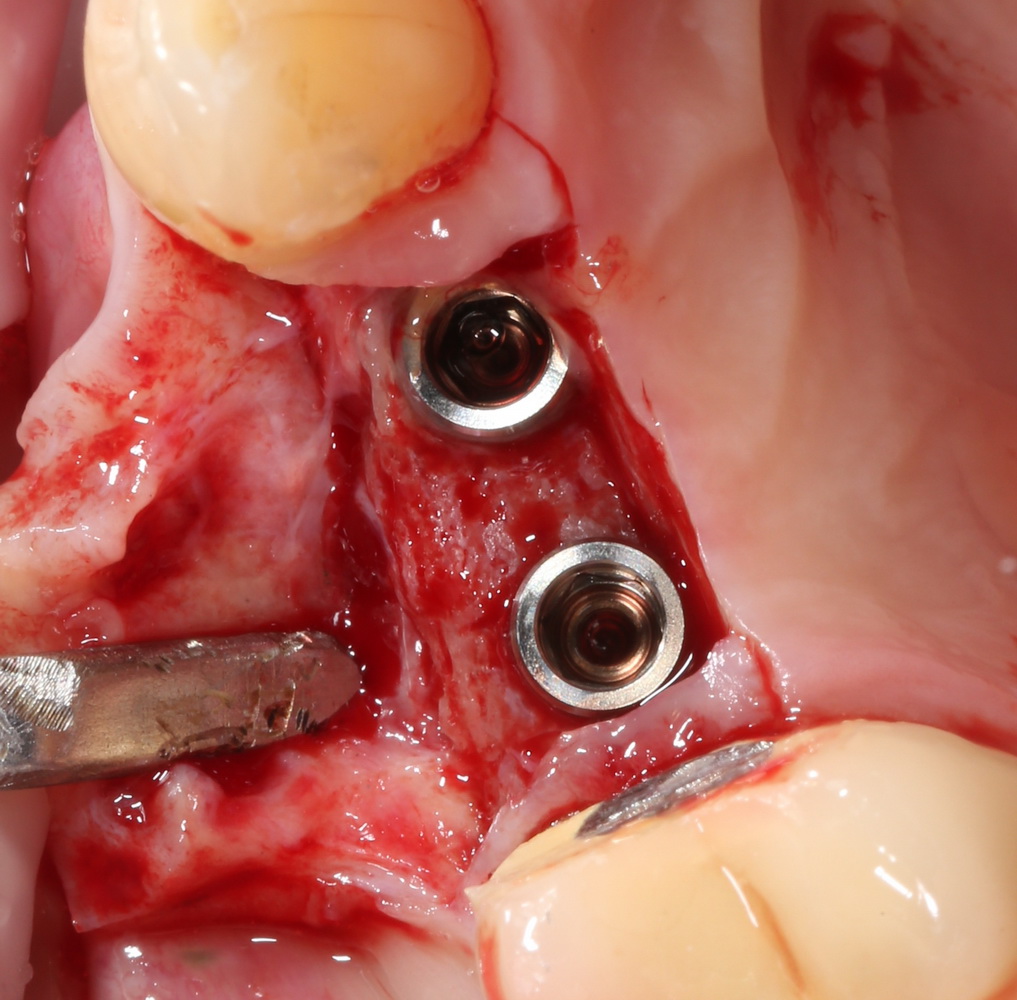

Делаем разрез, смотрим, что там с имплантами. А с ними всё в порядке:

Как и с окружающей их костной тканью:

Обратите внимание, до какого уровня имплантат находится в костной ткани. До полированной фаски — и это правильное расположение и глубина погружения XiVE. У разных имплантационных систем они могут отличаться — см. инструкцию.